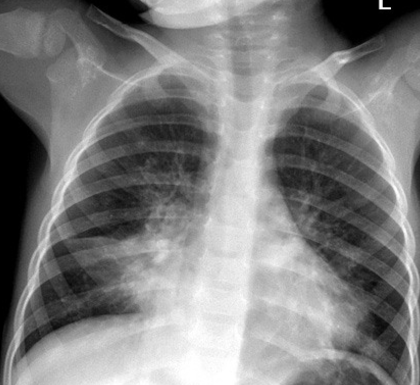

what does this show

LLL collapse